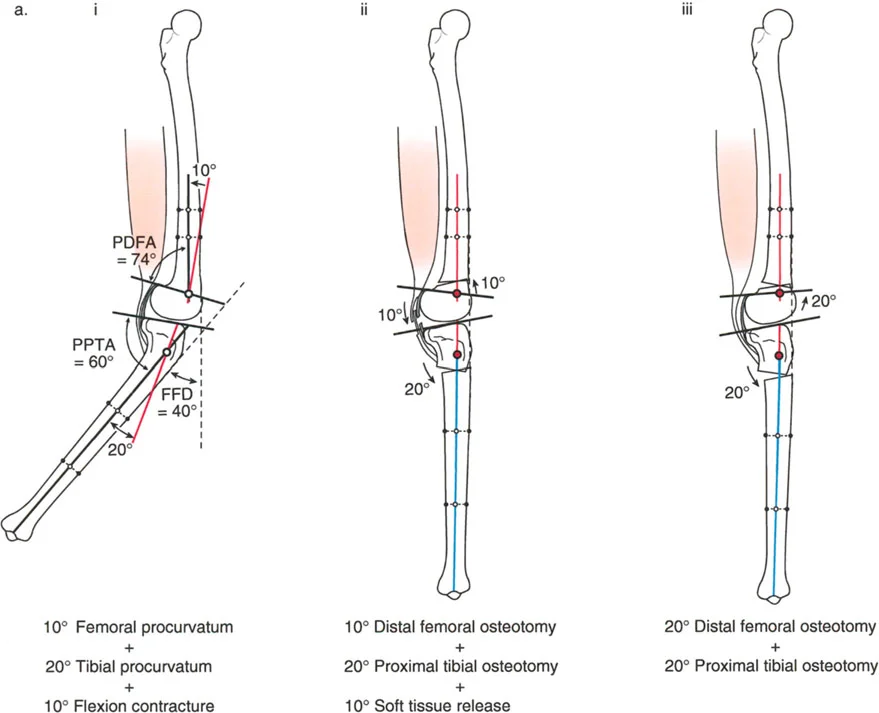

تصحيح تحدد حركة الركبة (Flexion Deformity - FFD)

تحدُّد حركة الركبة هو عدم القدرة على مد الركبة بالكامل. يمكن أن يكون سببه عظميًا أو ناتجًا عن تقلص في الأنسجة الرخوة.

- التشخيص الدقيق: يجب تحديد ما إذا كان تحدد الحركة ناتجًا عن تشوه عظمي (تقوس أمامي في الفخذ أو الساق) أو تقلص في الأنسجة الرخوة (الأوتار الخلفية، محفظة المفصل).

- قطع العظم التمديدي (Extension Osteotomy):

- إذا كان التشوه عظميًا، يتم إجراء قطع عظم تمديدي في عظم الفخذ أو الساق لتصحيح التقوس.

- الأستاذ الدكتور محمد هطيف يؤكد على أهمية عدم تصحيح الساق بأكثر من 90 درجة PPTA لتجنب فقدان الميل الخلفي الطبيعي للساق.

- تحرير الأنسجة الرخوة (Soft Tissue Release):

- إذا كان السبب هو تقلص الأنسجة الرخوة، فقد يتم إجراء إطالة للأوتار أو تحرير لمحفظة المفصل.

- إزالة النتوءات العظمية (Osteophyte Resection):

- إذا كانت النتوءات العظمية الأمامية تمنع المد الكامل، يمكن إزالتها جراحيًا.

- التصحيح التدريجي: في حالات تحدد الحركة الشديدة أو المعقدة، قد يكون التصحيح التدريجي باستخدام التثبيت الخارجي هو الخيار الأكثر أمانًا.